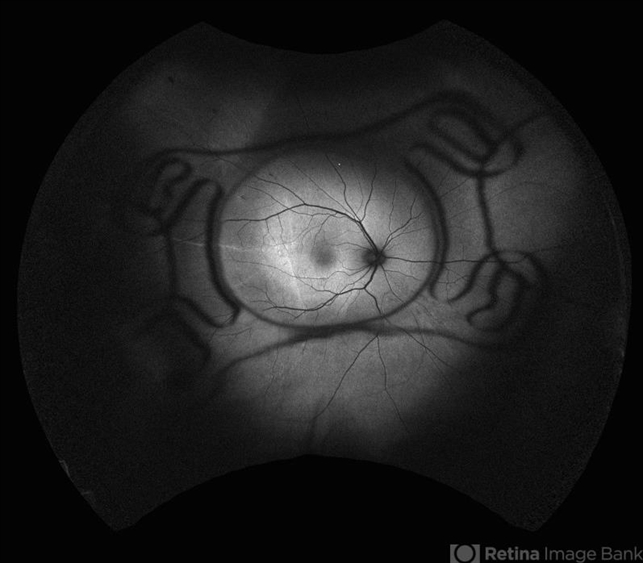

- Optos Silverstone fundus image of a 54-year-old man after 4 point scleral fixation Akreos AO60 with Gore Tex suture plus PPV who had a severe traumatic iris defect and was aphakic after ocular trauma.